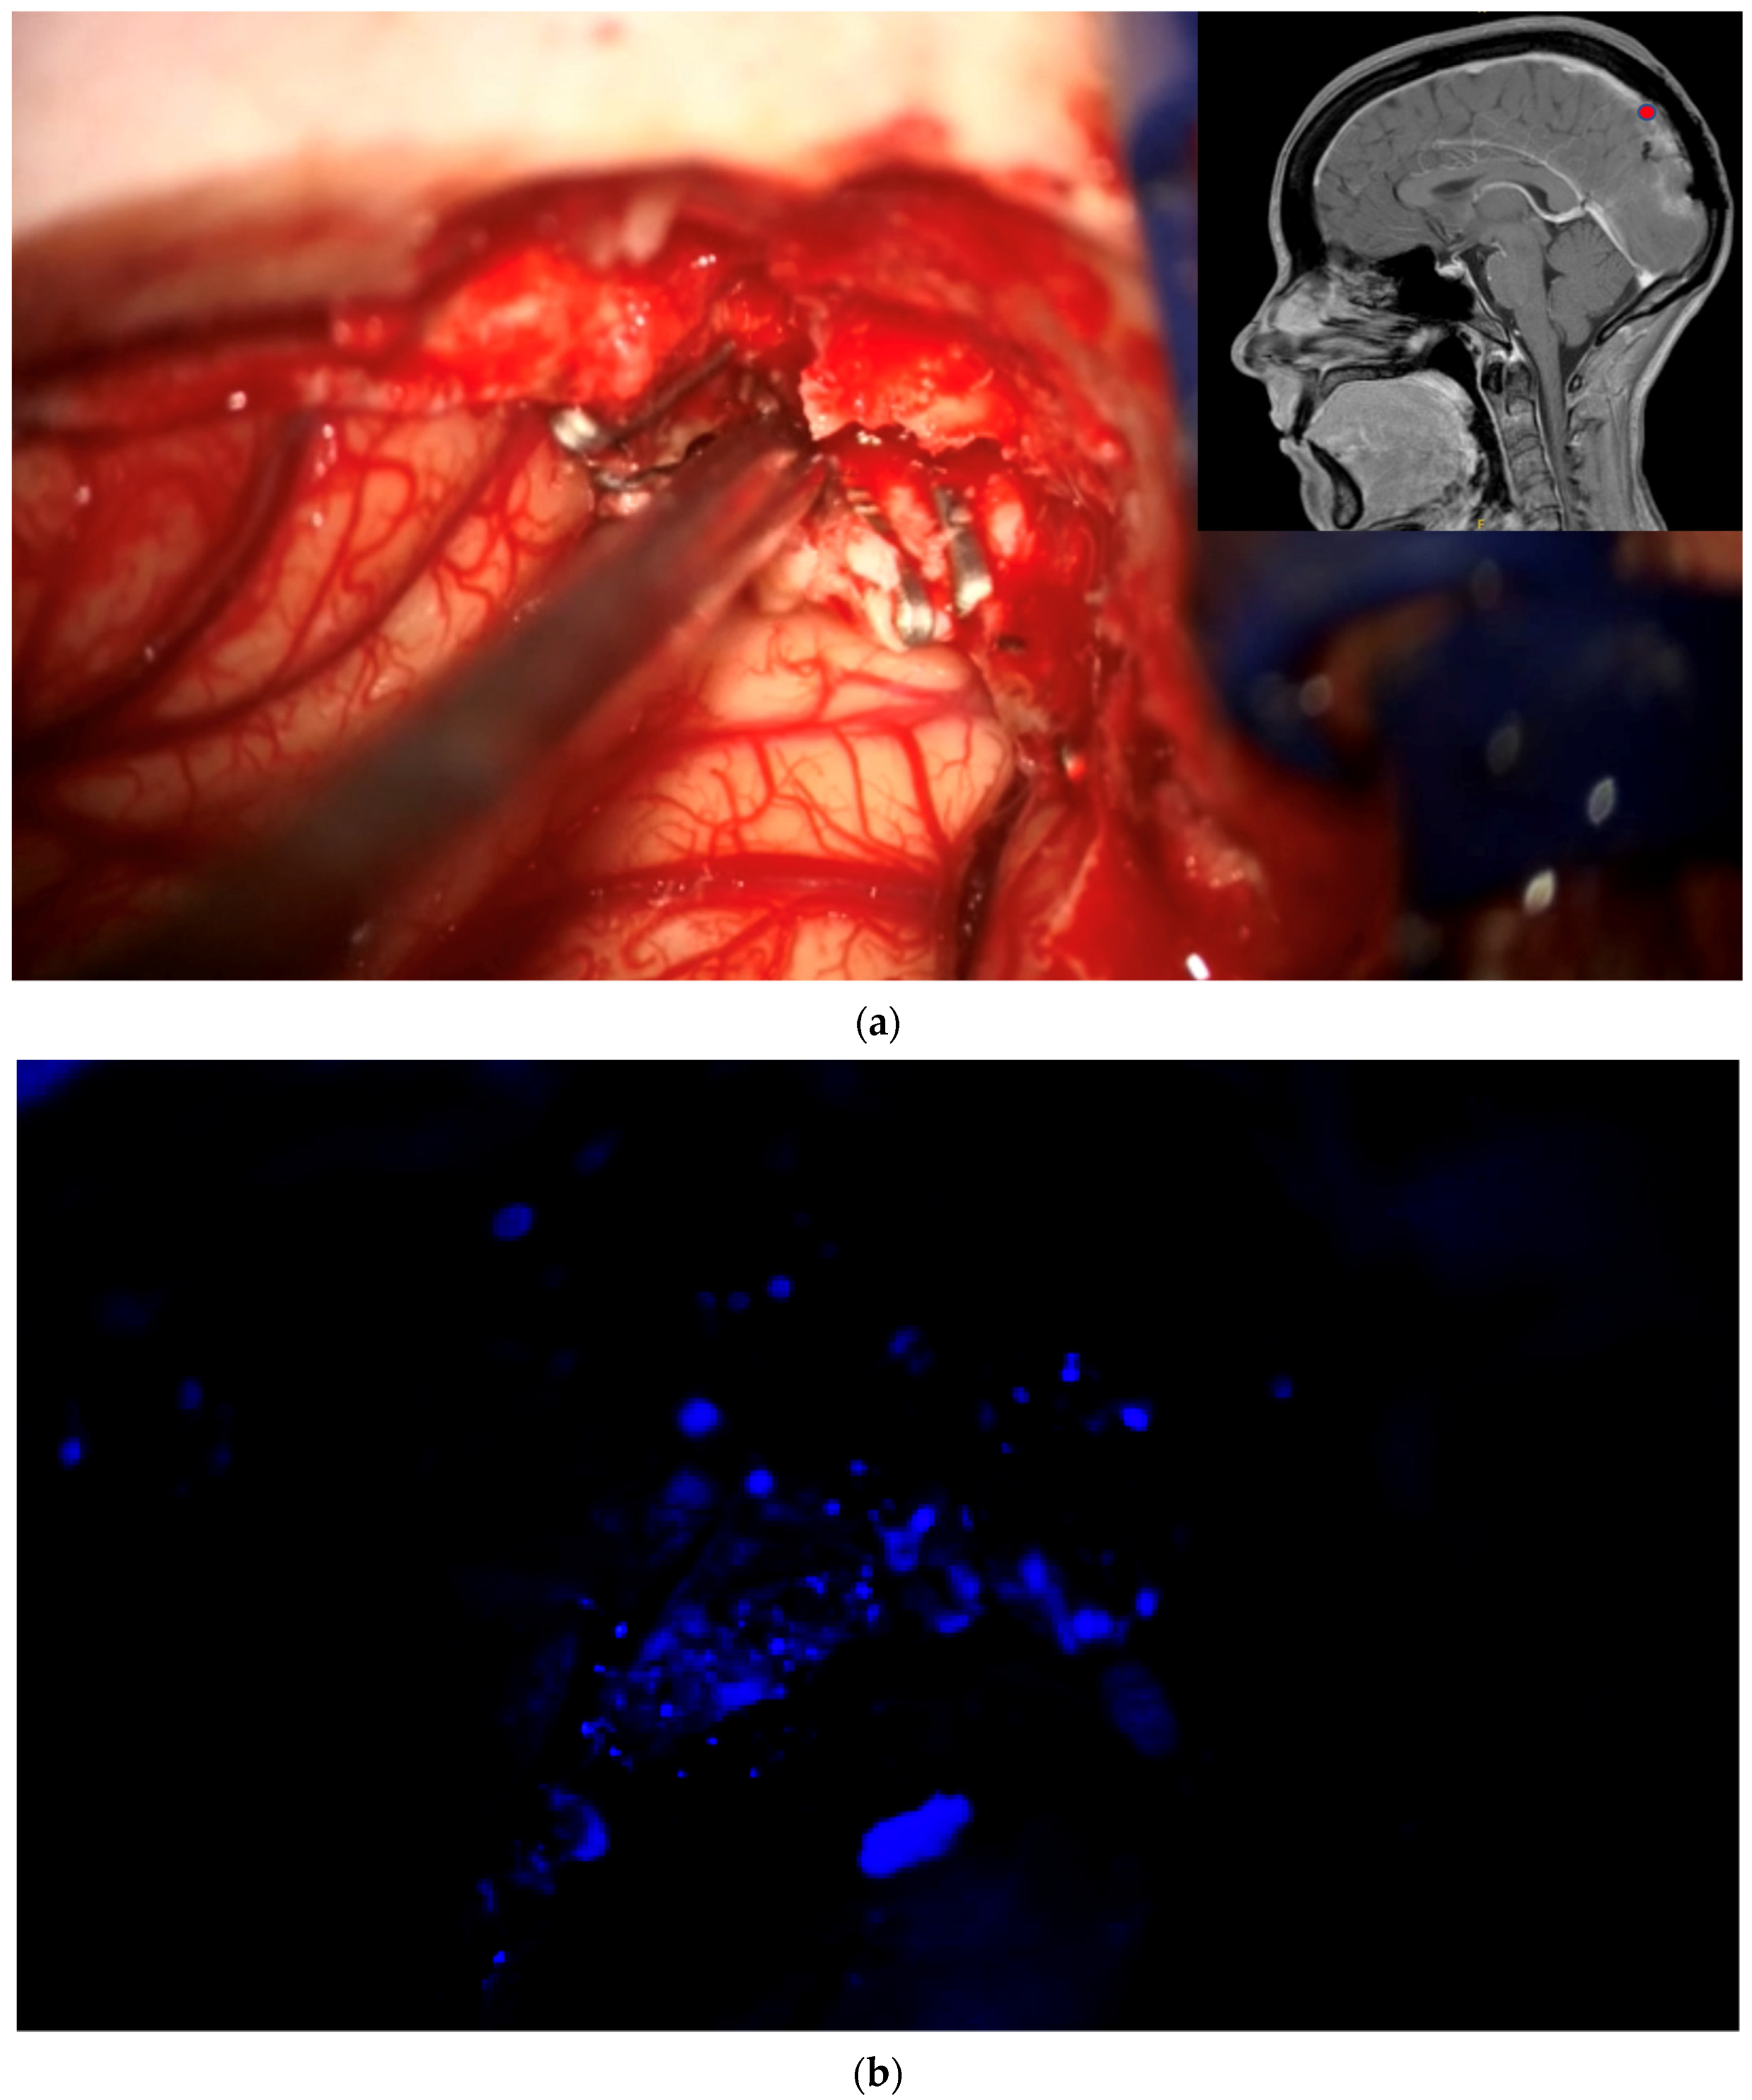

The aim of fluorescence assessment and tissue biopsy in bulk tumor is to determine whether a tumor shows fluorescence and to correlate fluorescence with tumor histology. To collect this biopsy, surgeons are asked to switch to blue light as soon as bulk tumor is encountered during surgery, to determine whether any fluorescence is visible and to take a biopsy from a fluorescing part of the tumor. A neuronavigation screenshot is taken from the exact location of the biopsy (Figure 1). The entire sequence is recorded using the microscope’s video system.

Biopsy acquisition from bulk tumor. As soon as surgeons encounter bulk tumor during surgery, they change to blue light, determine whether any fluorescence is visible, and, if so, take a biopsy from fluorescing tissue after taking a neuronavigation screenshot. The biopsy procedure is recorded for later assessment by the review panel. (a) Brain with visible bulk meningioma under elevated dura in a patient with tumor in the superior sagittal sinus infiltrating the adjacent brain. Insert shows pointer tip location marking the intended biopsy location. (b) Strong fluorescence of tumor under blue light, which is biopsied. (c) Neuronavigation screenshot (“F”: footwards; “H”: headward; “A”: anterior; “P”: posterior; “L”: left).